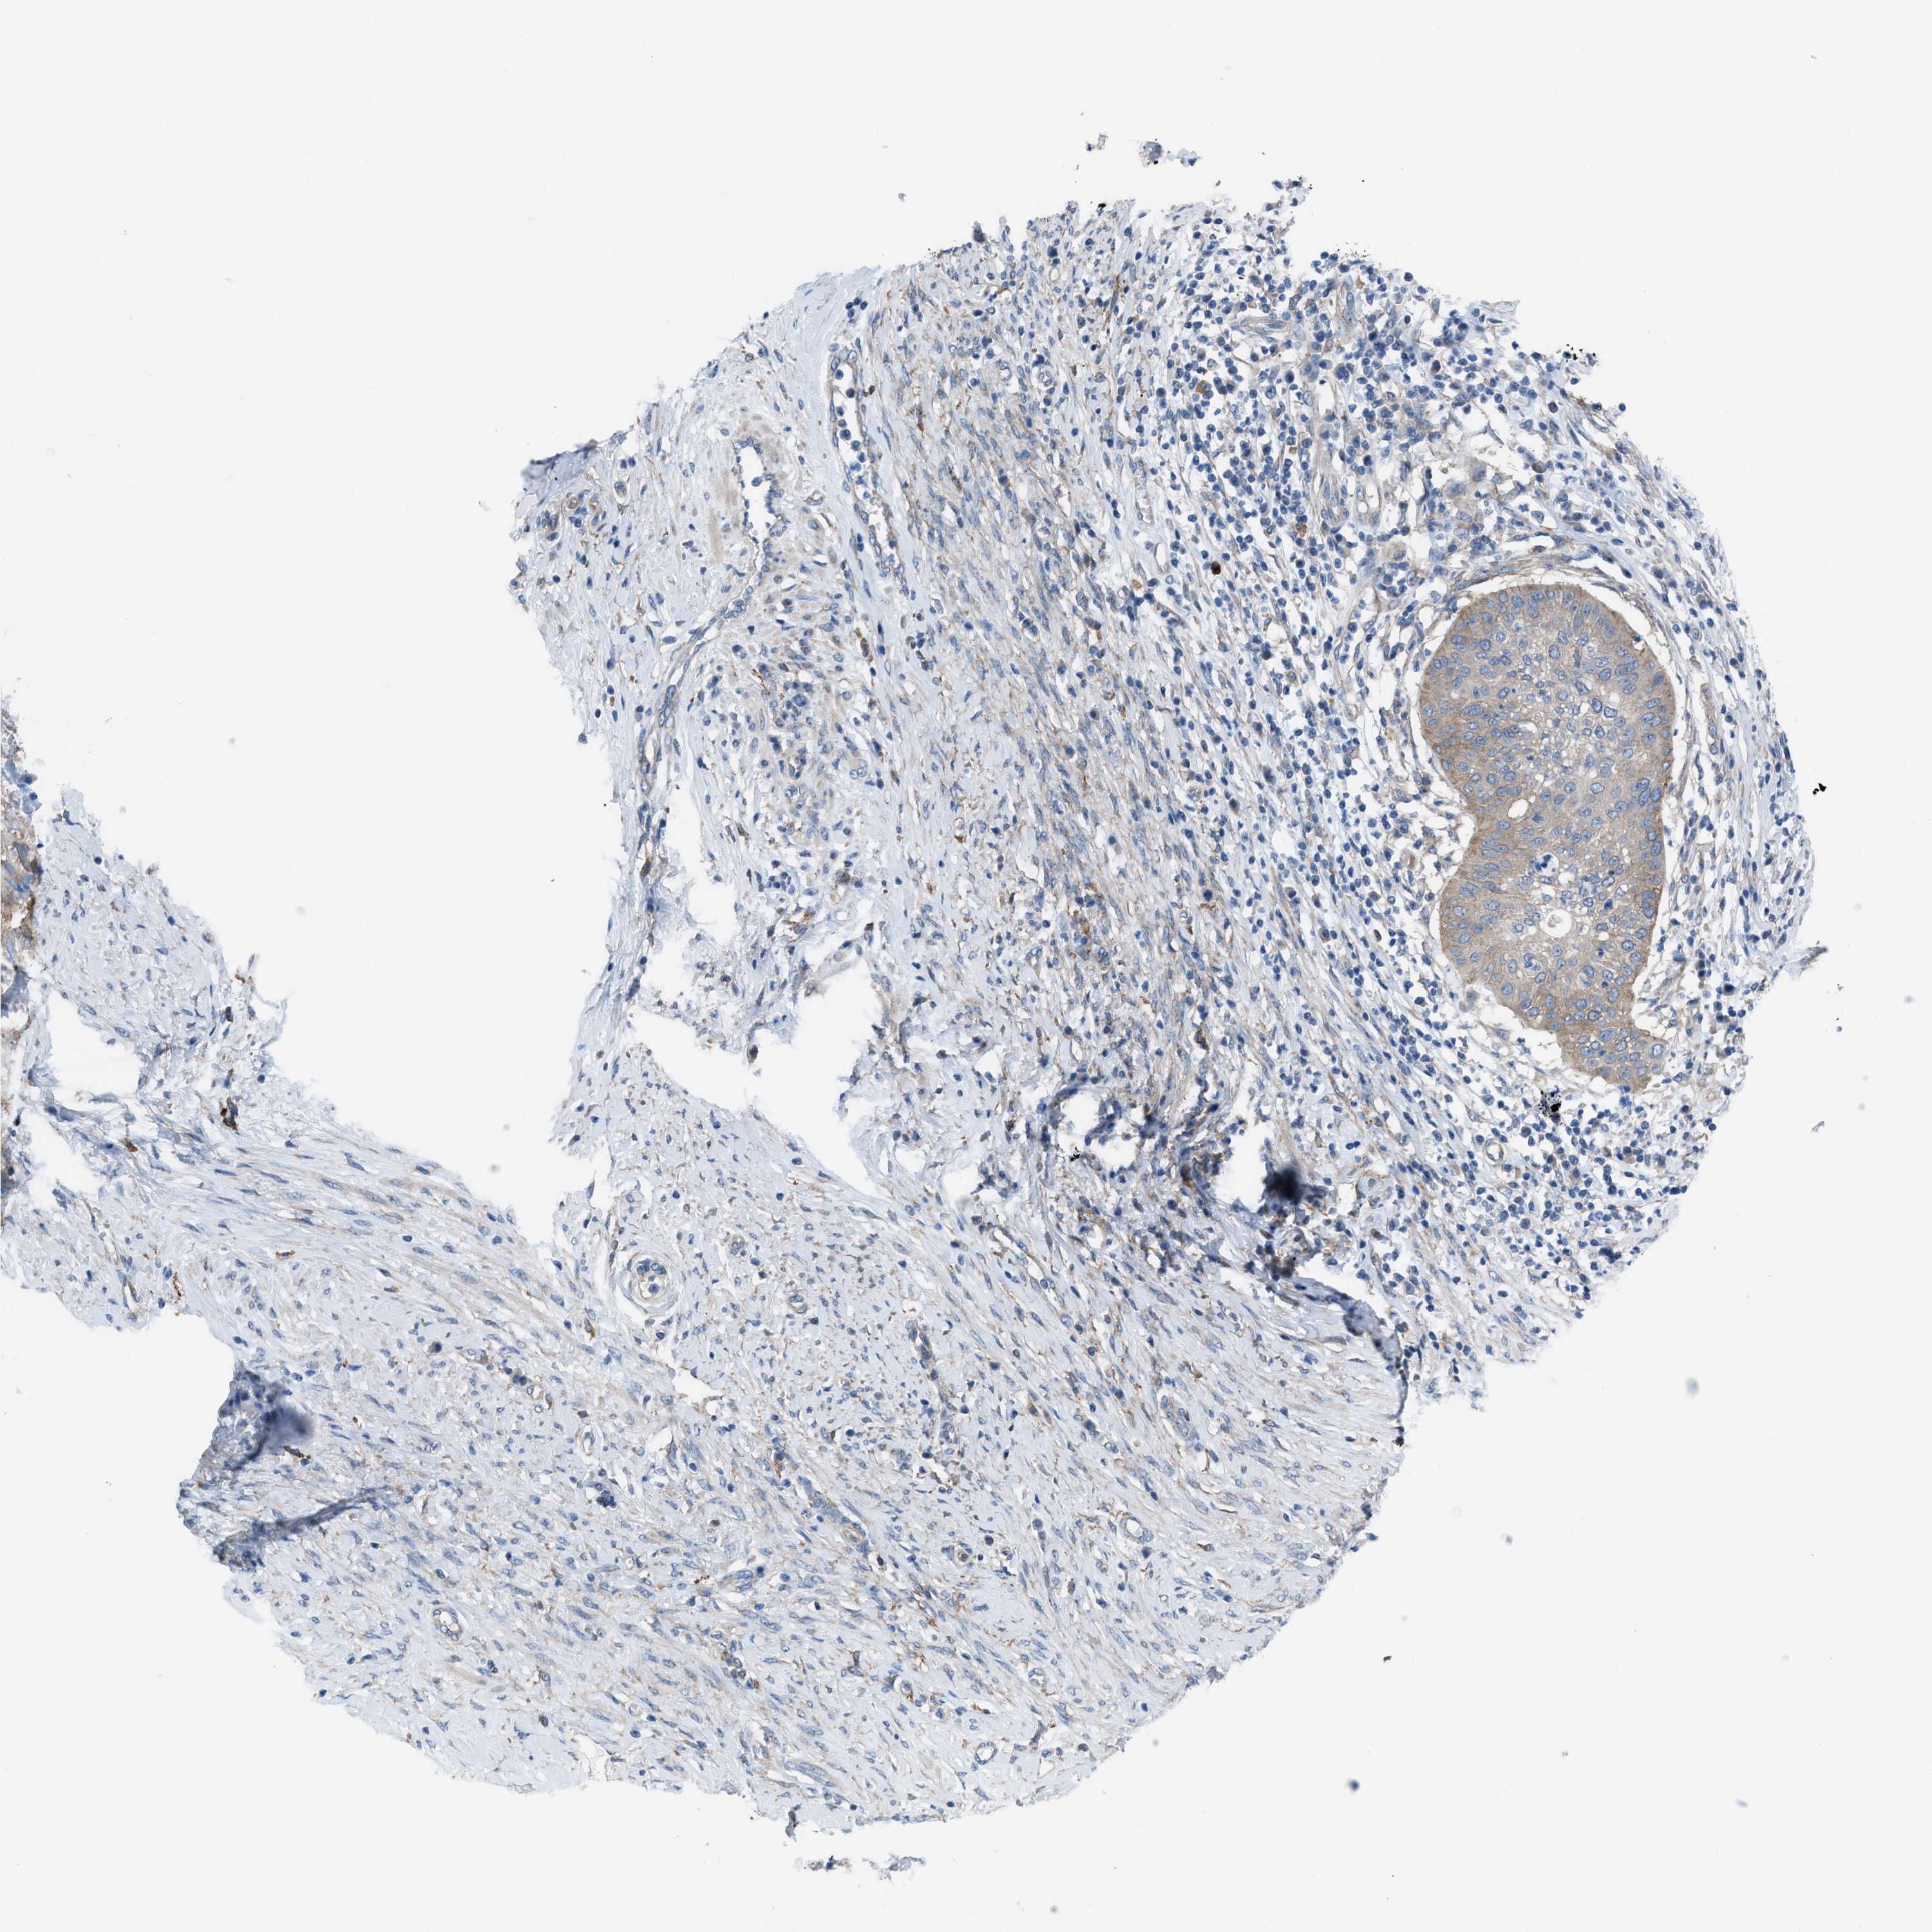

CERVICAL CANCER - Protein expressioni

A mouse-over function shows sample information and annotation data. Click on an image to view it in a full screen mode. Samples can be filtered based on level of antibody staining by selecting one or several of the following categories: high, medium, low and not detected. The assay and annotation is described here.

Note that samples used for immunohistochemistry by the Human Protein Atlas do not correspond to samples in the TCGA dataset.

Antibody stainingi

Antibody staining in the annotated cell types in the current human tissue is reported as not detected, low, medium, or high, based on conventional immunohistochemistry profiling in selected tissues. This score is based on the combination of the staining intensity and fraction of stained cells.

Each image is clickable and will lead to virtual microscopy that enables deeper exploration of all samples and also displays staining intensity scores, fraction scores and subcellular localization as well as patient and tissue information for each sample.

HPA001200

HPA018530

CAB000035

CAB068186

CAB073534

CAB080313

CAB080314

CAB080473

CAB080475

CAB080506

CAB080507

CAB080509

CAB080510

CAB080511

Staining

High

Medium

Low

Not detected

Intensity

Strong

Moderate

Weak

Negative

Quantity

>75%

75%-25%

<25%

None

Location

Nuclear

Cytoplasmic/membranous

Cytoplasmic/membranous,nuclear

Adenocarcinoma, NOS

Squamous cell carcinoma, NOS